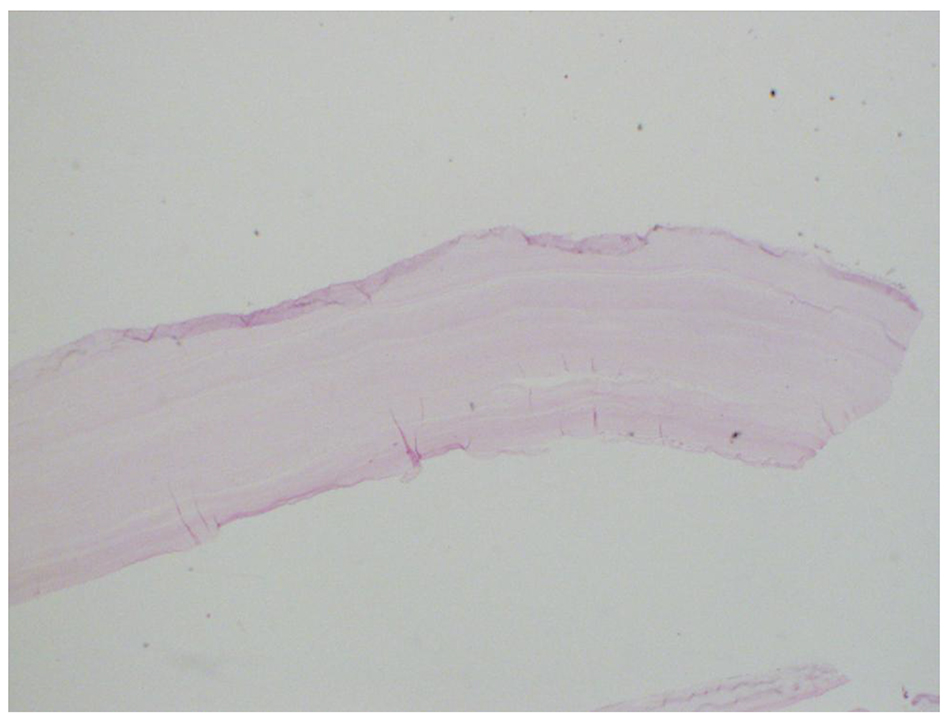

Based on the radiological and exposure history, albendazole (400 mg twice daily) and praziquanel 600 mg weekly were started for 4 weeks prior to surgery. Nephrectomy was done through retroperitoneal dissection of the kidney. The patient tolerated the procedure well with uneventful postoperative course. Macroscopic appearance showed an intact unilocular cyst filled with multiple cysts of 0.5 up to 5 cm in size (Fig. 5). On microscopy, the cyst showed a characteristic wall’s refractile eosinophilic lamination that is positive on PAS (Fig. 6). The uninvolved kidney shows chronic pyelonephritis, diabetic nephropathy and arteriosclerosis. She was discharged on albendazole 400 mg BD for another 4 weeks.

![]() Click for large image | Figure 6. Histopathology of resected hydatid “echinococcal” cyst. |